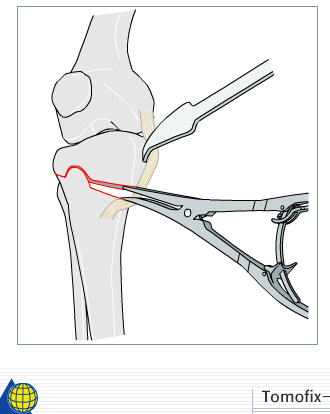

I prefer a medial opening wedge. Currently I prefer the tomofix system by synthes. Its instrumentation allows "dialing in" the correction nicely, and the fixed angle construct provides excellent stability. A few other companies have similar systems, Arthrex for example. Trying to hinge the correction on intact lateral cortex (1 cm.) is key to preserve stability.

4) if the correction is large( over 8 deg) or any cracks appear, or you put the limb axis in or beyond the neutral plane, so that the osteotomy is in tension rather than compression, then use a strong device( e.g. a Tomofix plate) rather than a minimal invasive device( e.g. a Pudu plate) - have both available if you're not sure, as the actual kit to do the osteotomy is a bit better on the Pudu set